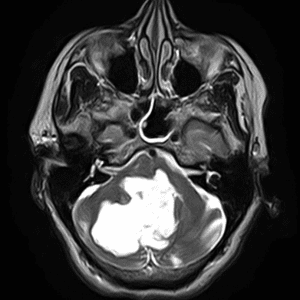

Kén sán não